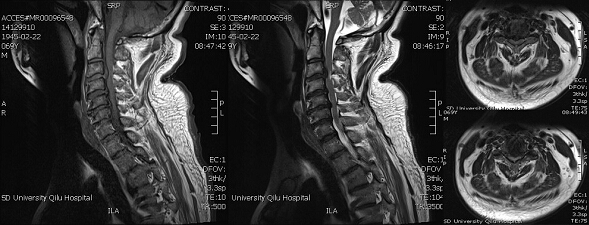

病例1:患者为一69岁老年男性,因颈部外伤后四肢麻木、无力2个月入院。患者于2个月前晚上在床边咳嗽时不慎摔下,当即意识不清,约10分钟后苏醒,四肢不能活动,大小便失禁。急诊于当地医院行颈椎MRI示:颈髓损伤,颈椎间盘突出(图1)。保守治疗两个月,效果差。入院诊断:1.颈髓损伤;2.颈椎间盘突出;3.颈椎管狭窄。

图1

患者入院后给予进一步完善相关检查,制定了详细的诊断和治疗计划:行颈椎CT三维重建及颈椎平片了解颈椎退变情况。患者MRI示颈3/4、4/5、5/6多节段椎间盘突出并椎管狭窄,可选择颈前路及颈后路两种手术方式。江玉泉主任带领神经外科脊柱脊髓专业组充分讨论患者病情,制定了微创颈前入路颈3/4椎间盘切除并椎间融合的手术方案。